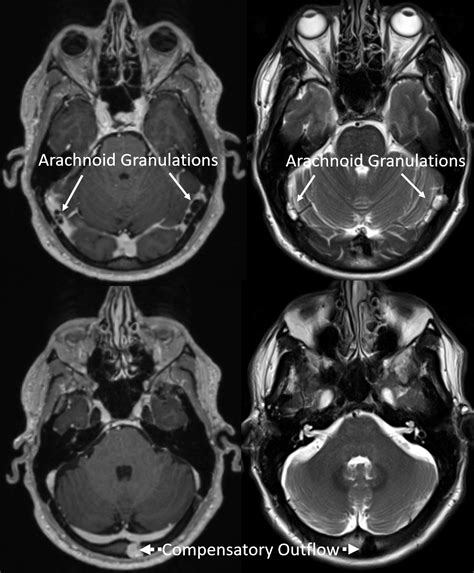

• Idiopathic Intracranial Hypertension (IIH): High pressure of the fluid surrounding the brain can sometimes manifest as a whooshing sound.

• Imaging Studies: MRIs or CT scans are frequently used to visualize the blood vessels in the head and neck.